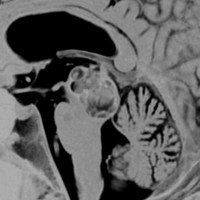

脳幹部の海綿状血管腫 brainstem cavernous hemangioma

2度の延髄内出血を生じた海綿状血管腫です。でも初回の出血からすでに27年間がたちます。症状も回復して麻痺もなくていまは社会生活に困ることはありません。脳幹部の海綿状血管腫の中には1ヶ月に何回もひどい出血を繰り返すのもあるのですが,この例のように30年近い間に軽い出血が2回だけというのもあります。残念ながら正確にこれを予測することはできません。この患者さんの海綿状血管腫は手術で摘出すれば麻痺などの合併症の可能性があるのでしません。

脳幹部の海綿状血管腫を手術した方がいいかどうかはすごく慎重に判断しないといけないのです。場合によってはとても重い後遺症が手術ででてしまうこともあります。もちろん手術ですごく症状がよくなってとても元気に暮らしている患者さんもたくさんいますが,そうでない患者さんもいるのです。手術を決意する前に,少なくとももう一人の脳外科医からセカンドオピニオンを聞きましょう。